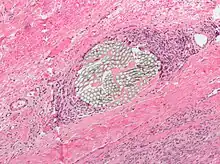

Also known as xanthelasmatic giant cells, Touton giant cells consist of fused epithelioid macrophages and have multiple nuclei. They are characterized by the ring-shaped arrangement of their nuclei and the presence of foamy cytoplasm surrounding the nucleus. Touton giant cells have been observed in lipid-laden lesions such as fat necrosis.

Foreign-body giant cells form when a subject is exposed to a foreign substance. Exogenous substances can include talc or sutures. As with other types of giant cells, epithelioid macrophages fusing together causes these giant cells to form and grow.[13] In this form of giant cell, the nuclei are arranged in an overlapping manner. This giant cell is often found in tissue because of medical devices, prostheses, and biomaterials.